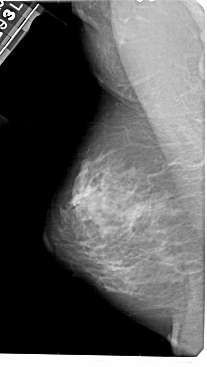

A_1447_1.LEFT_CC

LEFT_CC LINES 5101 PIXELS_PER_LINE 2806 BITS_PER_PIXEL 12 RESOLUTION 43.5 NON_OVERLAY